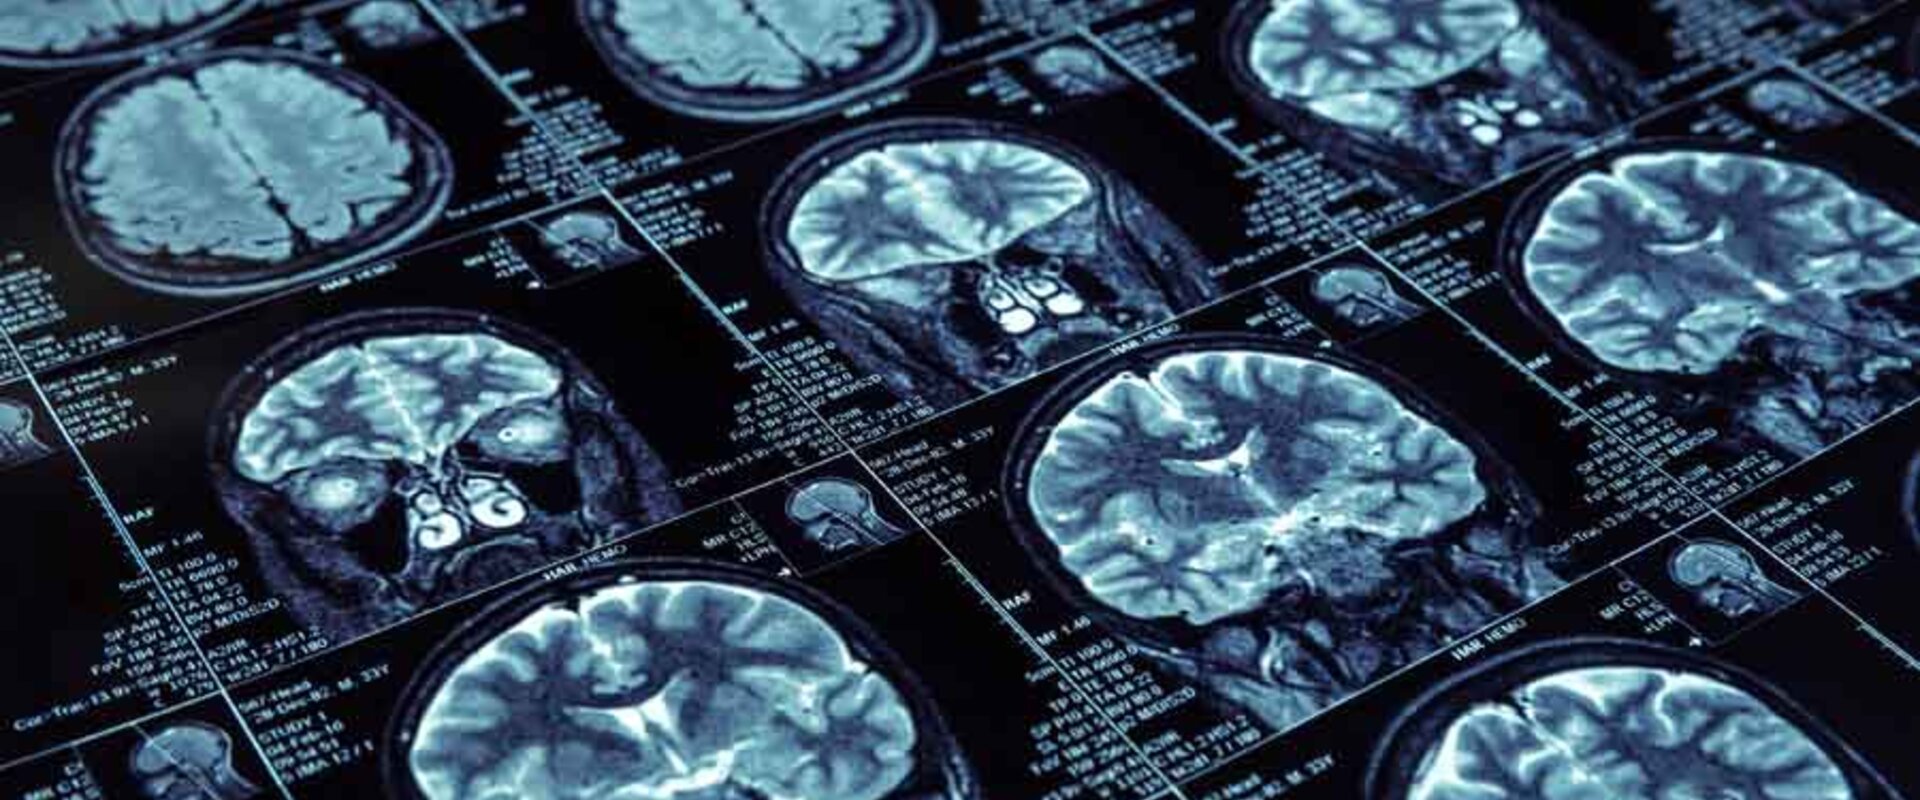

High resolution brain scans

Magnetic Resonance Imaging (MRI) is a highly effective technique for peering into the body and looking for evidence of serious problems such as tumours and damaged blood vessels. Over 30 million patients already have MRI examinations annually across the EU, and now higher resolution 7T MRI scanners are able to offer even better early disease diagnosis and the potential for detecting Alzheimer’s, Parkinson’s and Multiple Sclerosis.

The current IEC standard facilitates CE marking for 7T MRI scanners based on conformance to EU regulatory requirements. This now makes these ultra-high resolution MRI imaging machines available for clinical use, albeit with restrictions. Clinics will now have a more powerful imaging tool capable of enabling earlier diagnosis of serious and degenerative brain diseases and other treatable conditions creating the potential for earlier life-changing treatments. Future editions of the IEC standard will waive these current restrictions and broaden the range of 7T MRI uses in clinical medicine.